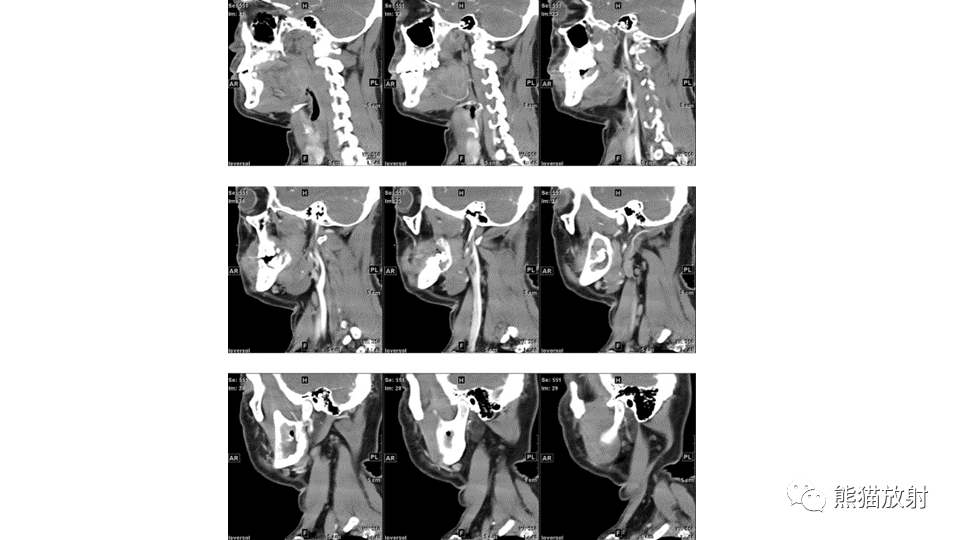

【病例】下颌骨成釉细胞瘤2例CT-8

【病例】下颌骨成釉细胞瘤2例CT-9

【病例】下颌骨成釉细胞瘤2例CT-10